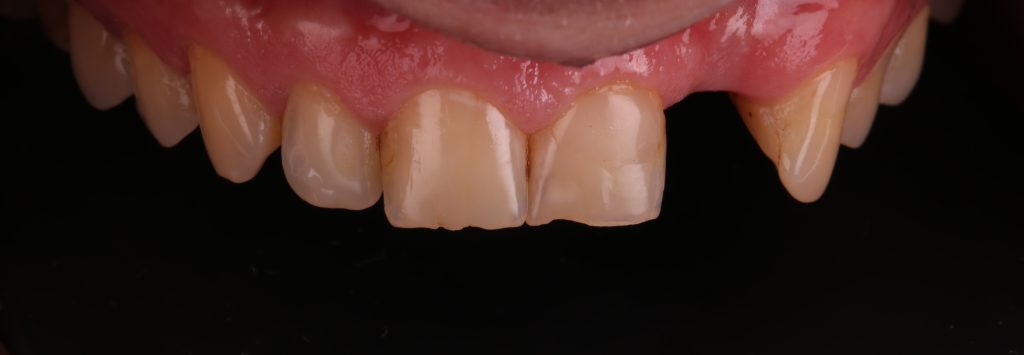

Пациент обратился с жалобами на отсутствующий зуб 2.2

Внешний вид ортопедической конструкции